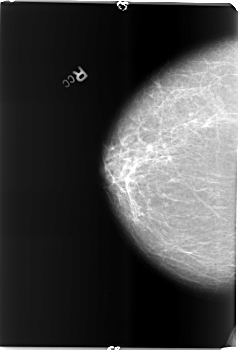

B_3494_1.RIGHT_CC

RIGHT_CC LINES 5936 PIXELS_PER_LINE 4032 BITS_PER_PIXEL 12 RESOLUTION 50 NON_OVERLAY